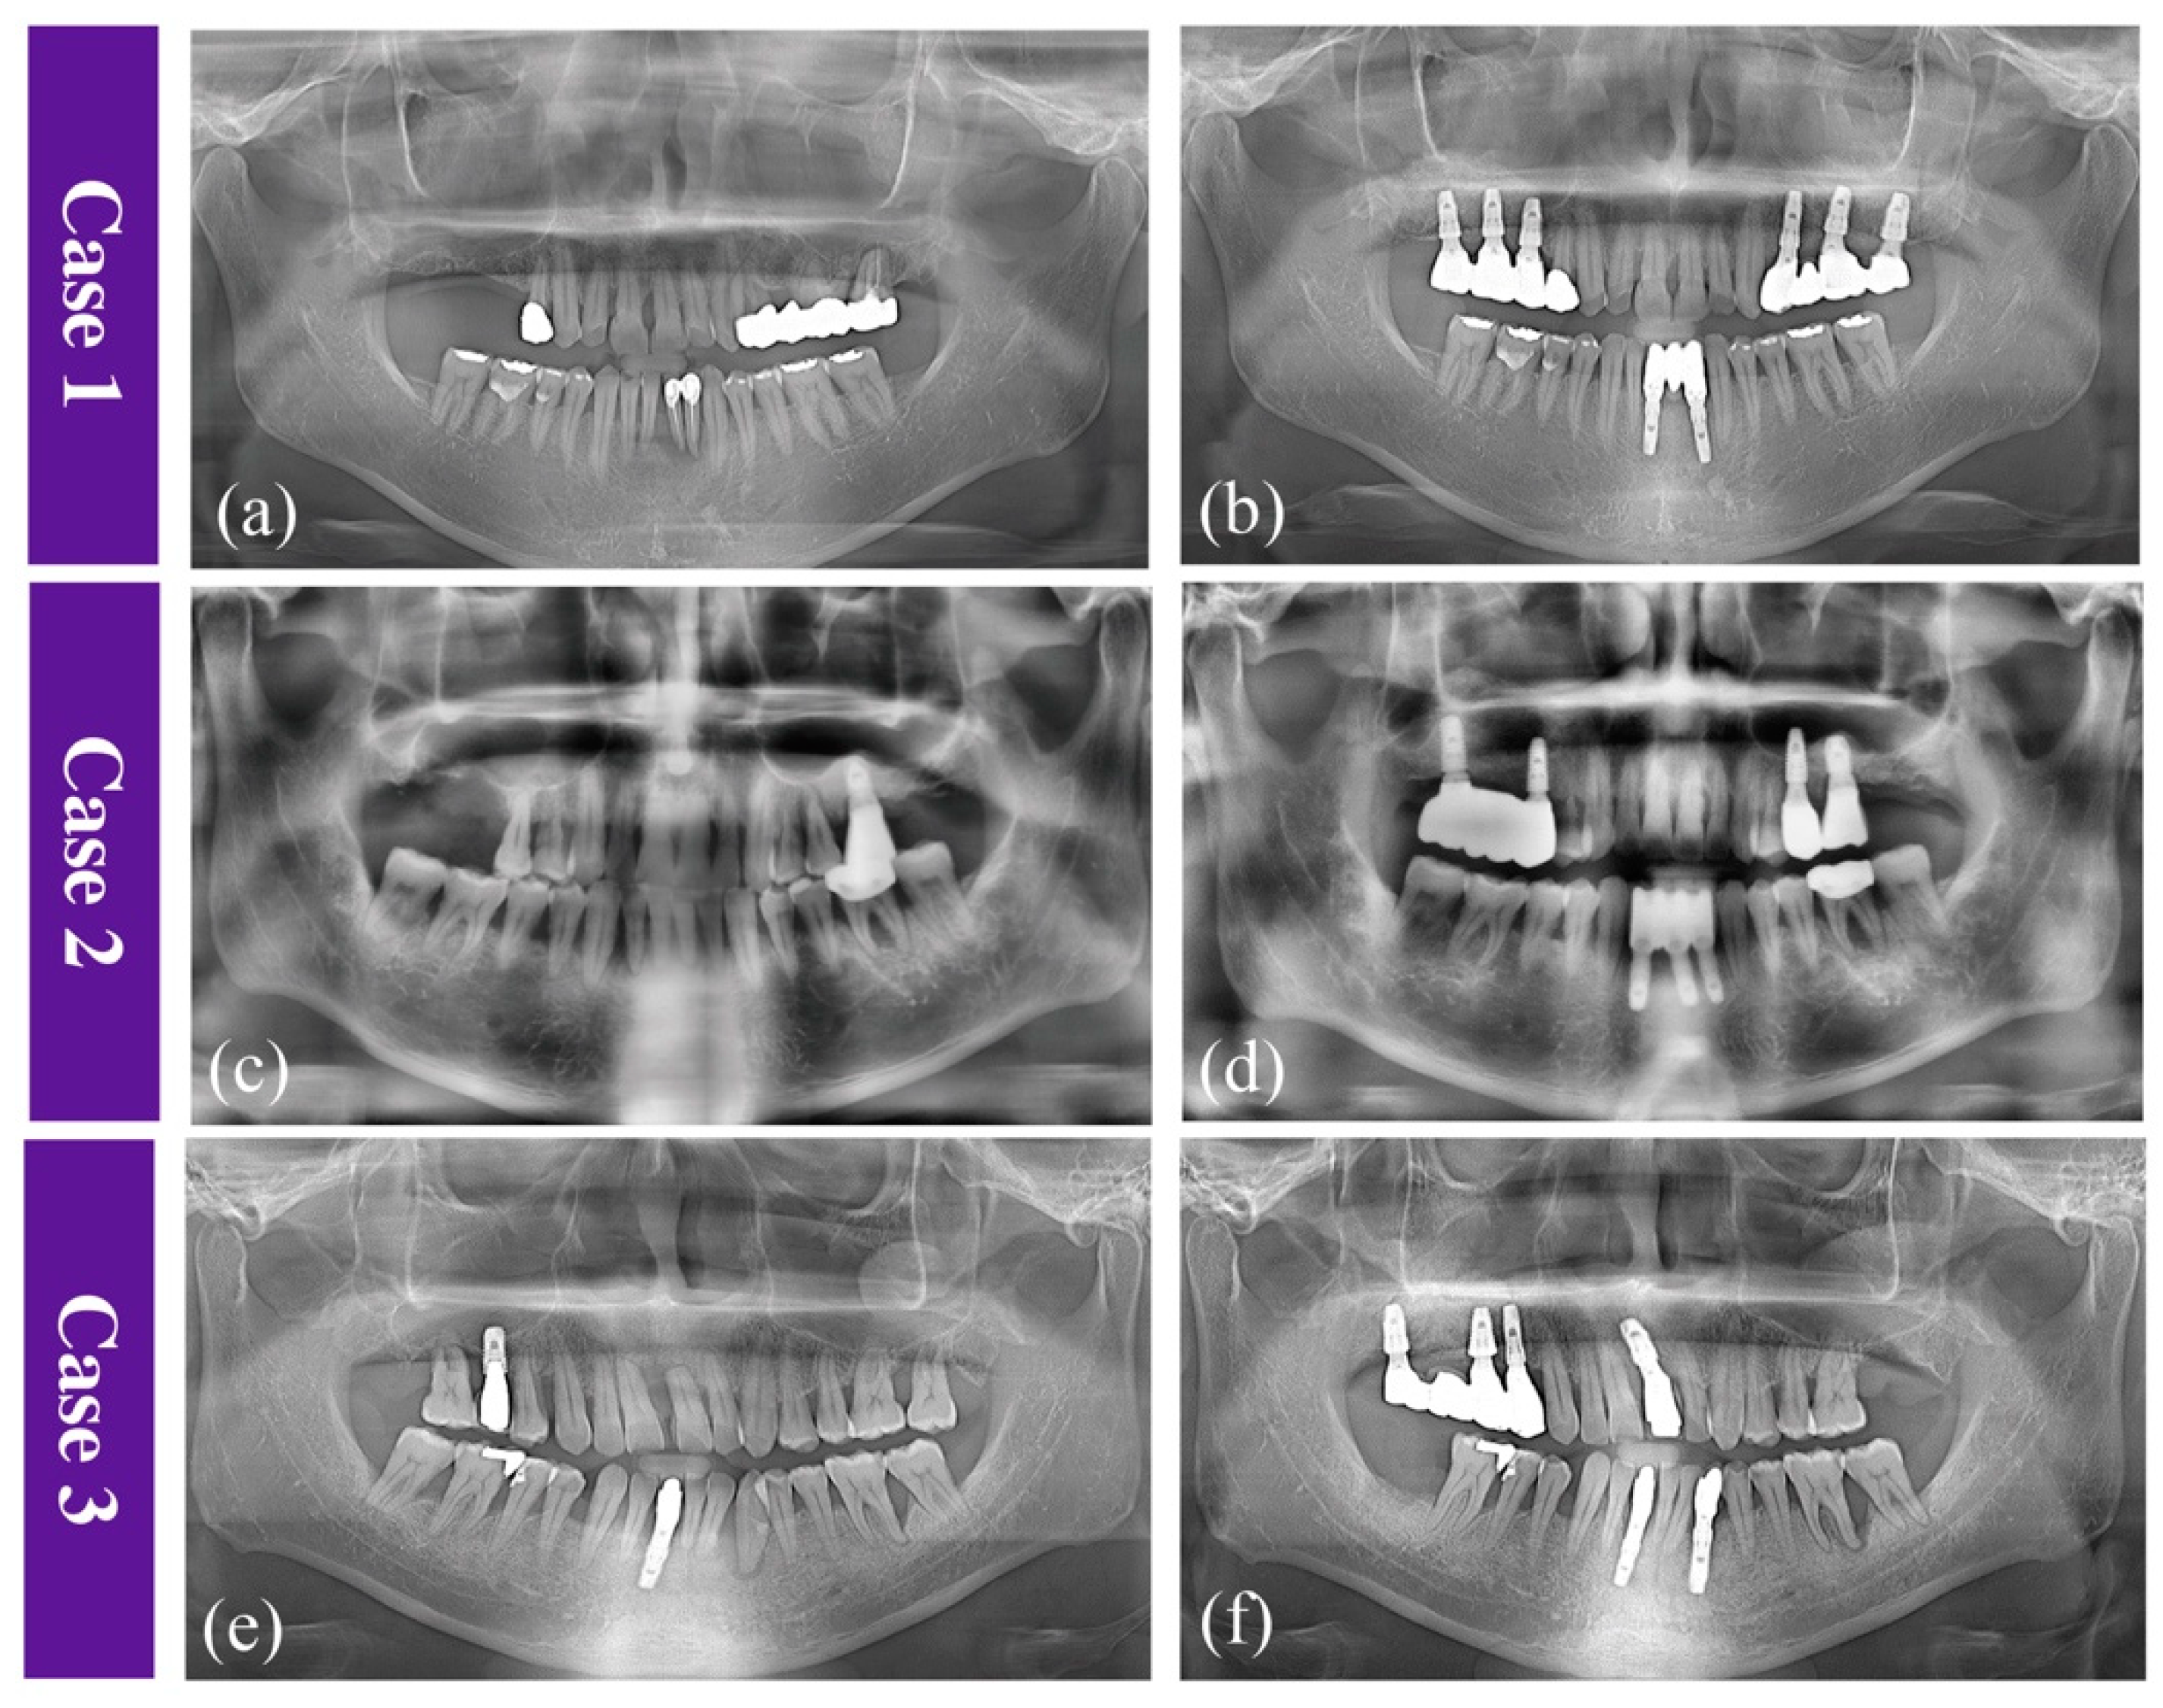

2.2.1. Case 1

2.2.2. Case 2

2.2.3. Case 3

2.5. Radiological Findings